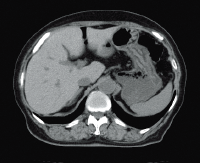

Клинические изображения

Для снижения лучевой нагрузки и повышения качества визуализации в КТ SUPRIA используются алгоритм интеллектуального перераспределения дозы IntelliEC и современный метод итерации IntelliIP, позволяющие провести сканирование с очень низкими значениями доз и получить изображения необходимого диагностического качества. В результате лучевая нагрузка на исследуемую область существенно снижается при сохранении высокого качества визуализации, особенно на уровне плотных паренхиматозных органов.